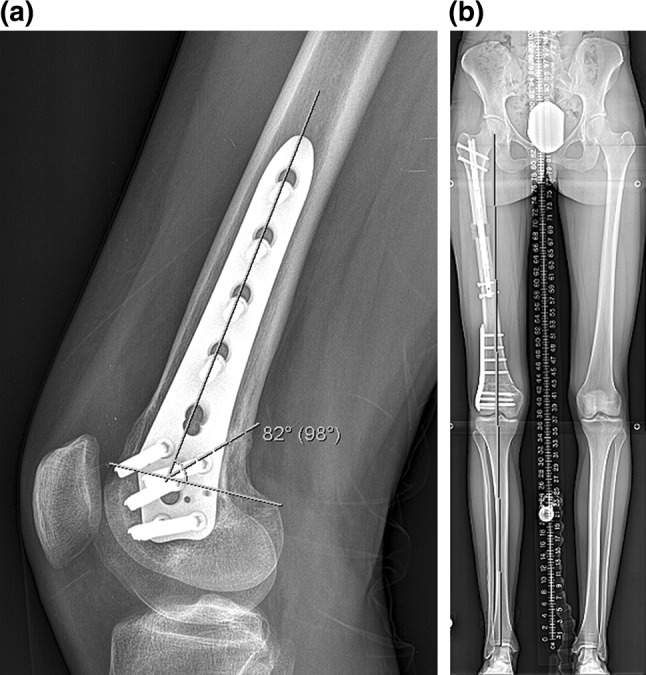

Fig. 8.

a This lateral femoral radiograph of patient 1 shows a PDFA of 82°, b this 51 in. standing film of patient 1 shows a MAD of 0 mm

Radiographic assessment showed the average amount of lengthening at the proximal osteotomy site was 40 mm (there was additional lengthening that occurred at the distal osteotomy site), and the residual LLD was 3 mm with the right leg shorter. The average post-op PDFA was 81° and MAD was 3 mm medial (Fig. 8a, b; Table 5). Bone healing index (days to consolidation from osteotomy date/cm lengthening) average was 24 days/cm (Table 5). All distal femoral osteotomy sites were healed at 3 months post-surgery. The distal osteotomy was located close to the knee joint. The average distance from the osteotomy to the knee joint line was 57 mm, and the distance from the osteotomy to the notch was 47 mm (Table 6).